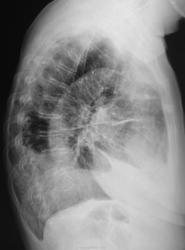

Фрагменты томограмм с увеличением.

Добавлены фрагменты томограмм с увеличением.

Мне кажется, что есть наличие образования по передней стенке, ретростернально.

Как мне кажется там их 2-а

Неужто тубплеврит? Полиморфные очаговые тени говорят сами за себя.